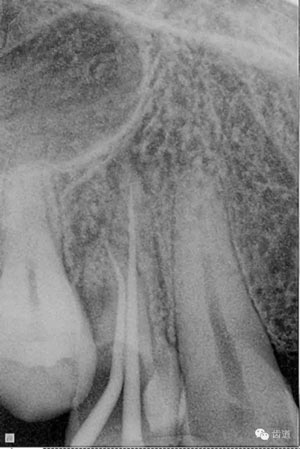

數(shù)碼x攝影顯示:近中頰根及腭根根管充填恰填,遠(yuǎn)中根管有遺漏。

顯微鏡下反復(fù)探查根管,未探及遺漏根管口,放置棉球,zoe暫封。轉(zhuǎn)診上級(jí)醫(yī)生處理。